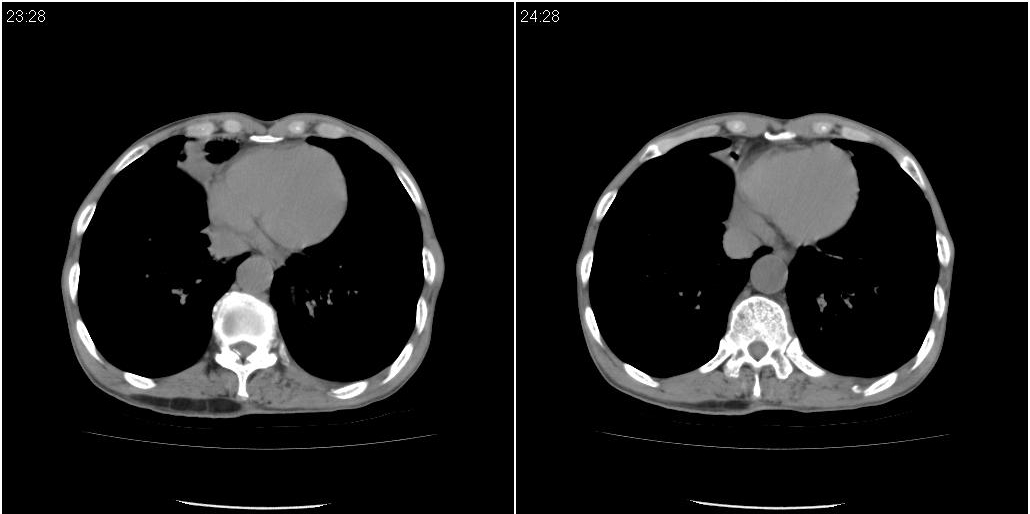

1)右肺中叶慢性炎症并支气管扩张,节段性肺不张。2)两肺下叶支气管扩张。

1)右肺中叶慢性炎症并支气管扩张,节段性肺不张。2)左肺下叶支气管扩张